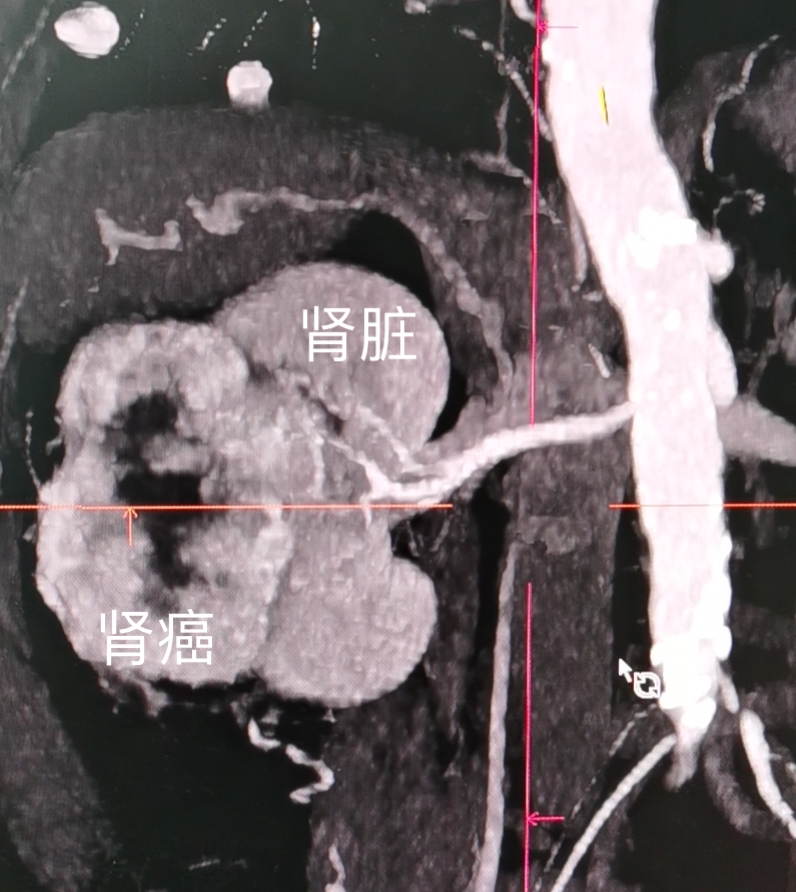

肾癌的CT表现

肿瘤呢包括肾上腺肿瘤、肾脏肿瘤、输尿管肿瘤、膀胱肿瘤、前列腺肿瘤、*丸睾**肿瘤、阴茎肿瘤及尿道肿瘤.对于泌尿系统肿瘤较为有特异性的是有部分的肿瘤比如说肾脏、输尿管、膀胱及前列腺的肿瘤容易出现血尿的表现.肾上腺肿瘤如果是有分泌激素功能的会出现对应的临床症状.